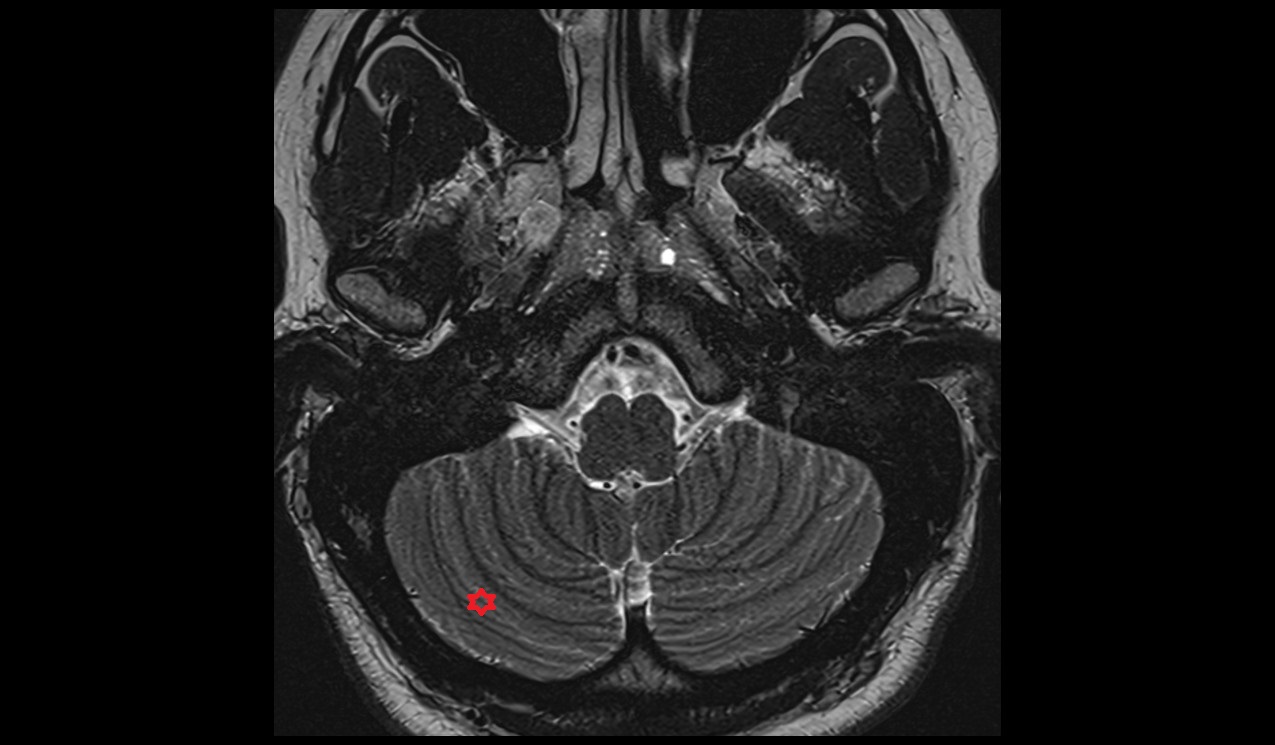

- Cerebellum

- Flocculus

- Nodule of vermis (X)

- Cerebellar tonsil (H IX)